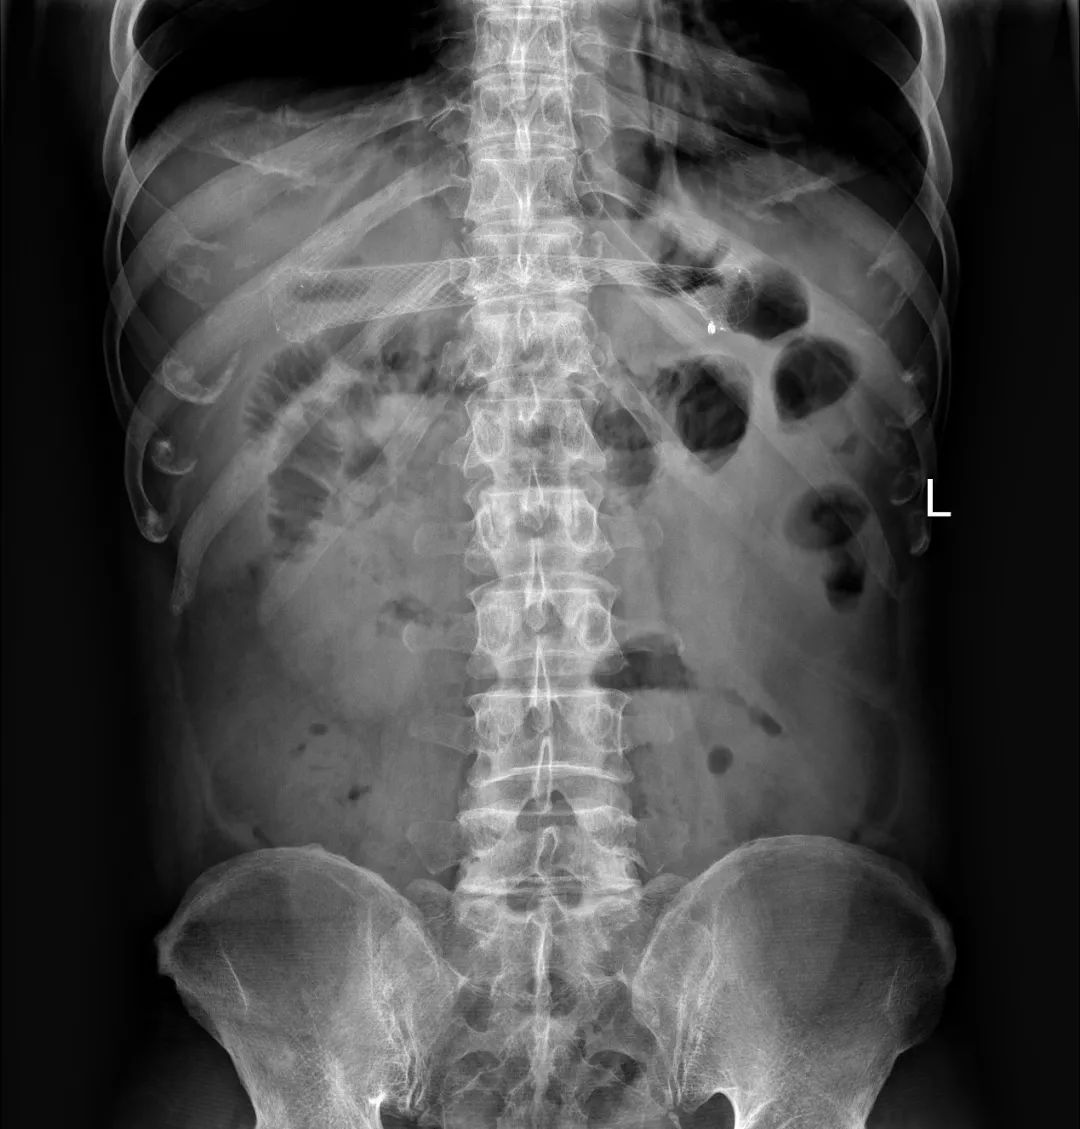

到此为止,患者已经接受了3次大的腹部手术,并接受了放化疗。但是,疾病仍然进展。2018年6月下旬患者出现恶心、呕吐,腹痛、腹胀,不能进食,X线腹部平片及腹部CT检查提示肠梗阻合并感染(见图1、图2),给予抗炎对症治疗效果差。结肠镜检查见横结肠占位伴梗阻(图3)。患者腹痛腹胀进行性加重,出现高热、血压下降等感染性休克症状。患者已经无法耐受再次开腹手术!

图1 腹部X线平片见扩张的肠管和气液平——典型的肠梗阻